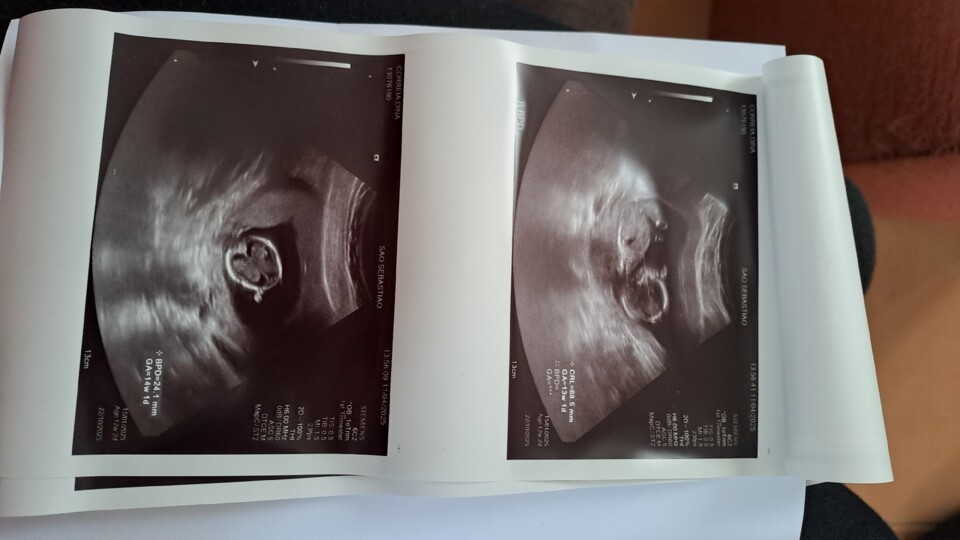

... tem uma cabeça, dois braços e duas pernas e um ❤️ que bate como uma metralhadora.

Fui à primeira ecografia e estou de 13 semanas e 1 dia.

E está tudo bem.

Terça-feira levei um susto e decidi ir às urgências, lá foi-me feita uma ecografia vaginal porque eu disse que me pareceu ter visto sangue na minha roupa íntima e aí descobri que estava já de 11 semanas. Esta semana completo 12 semanas, três meses. O 1° trimestre.